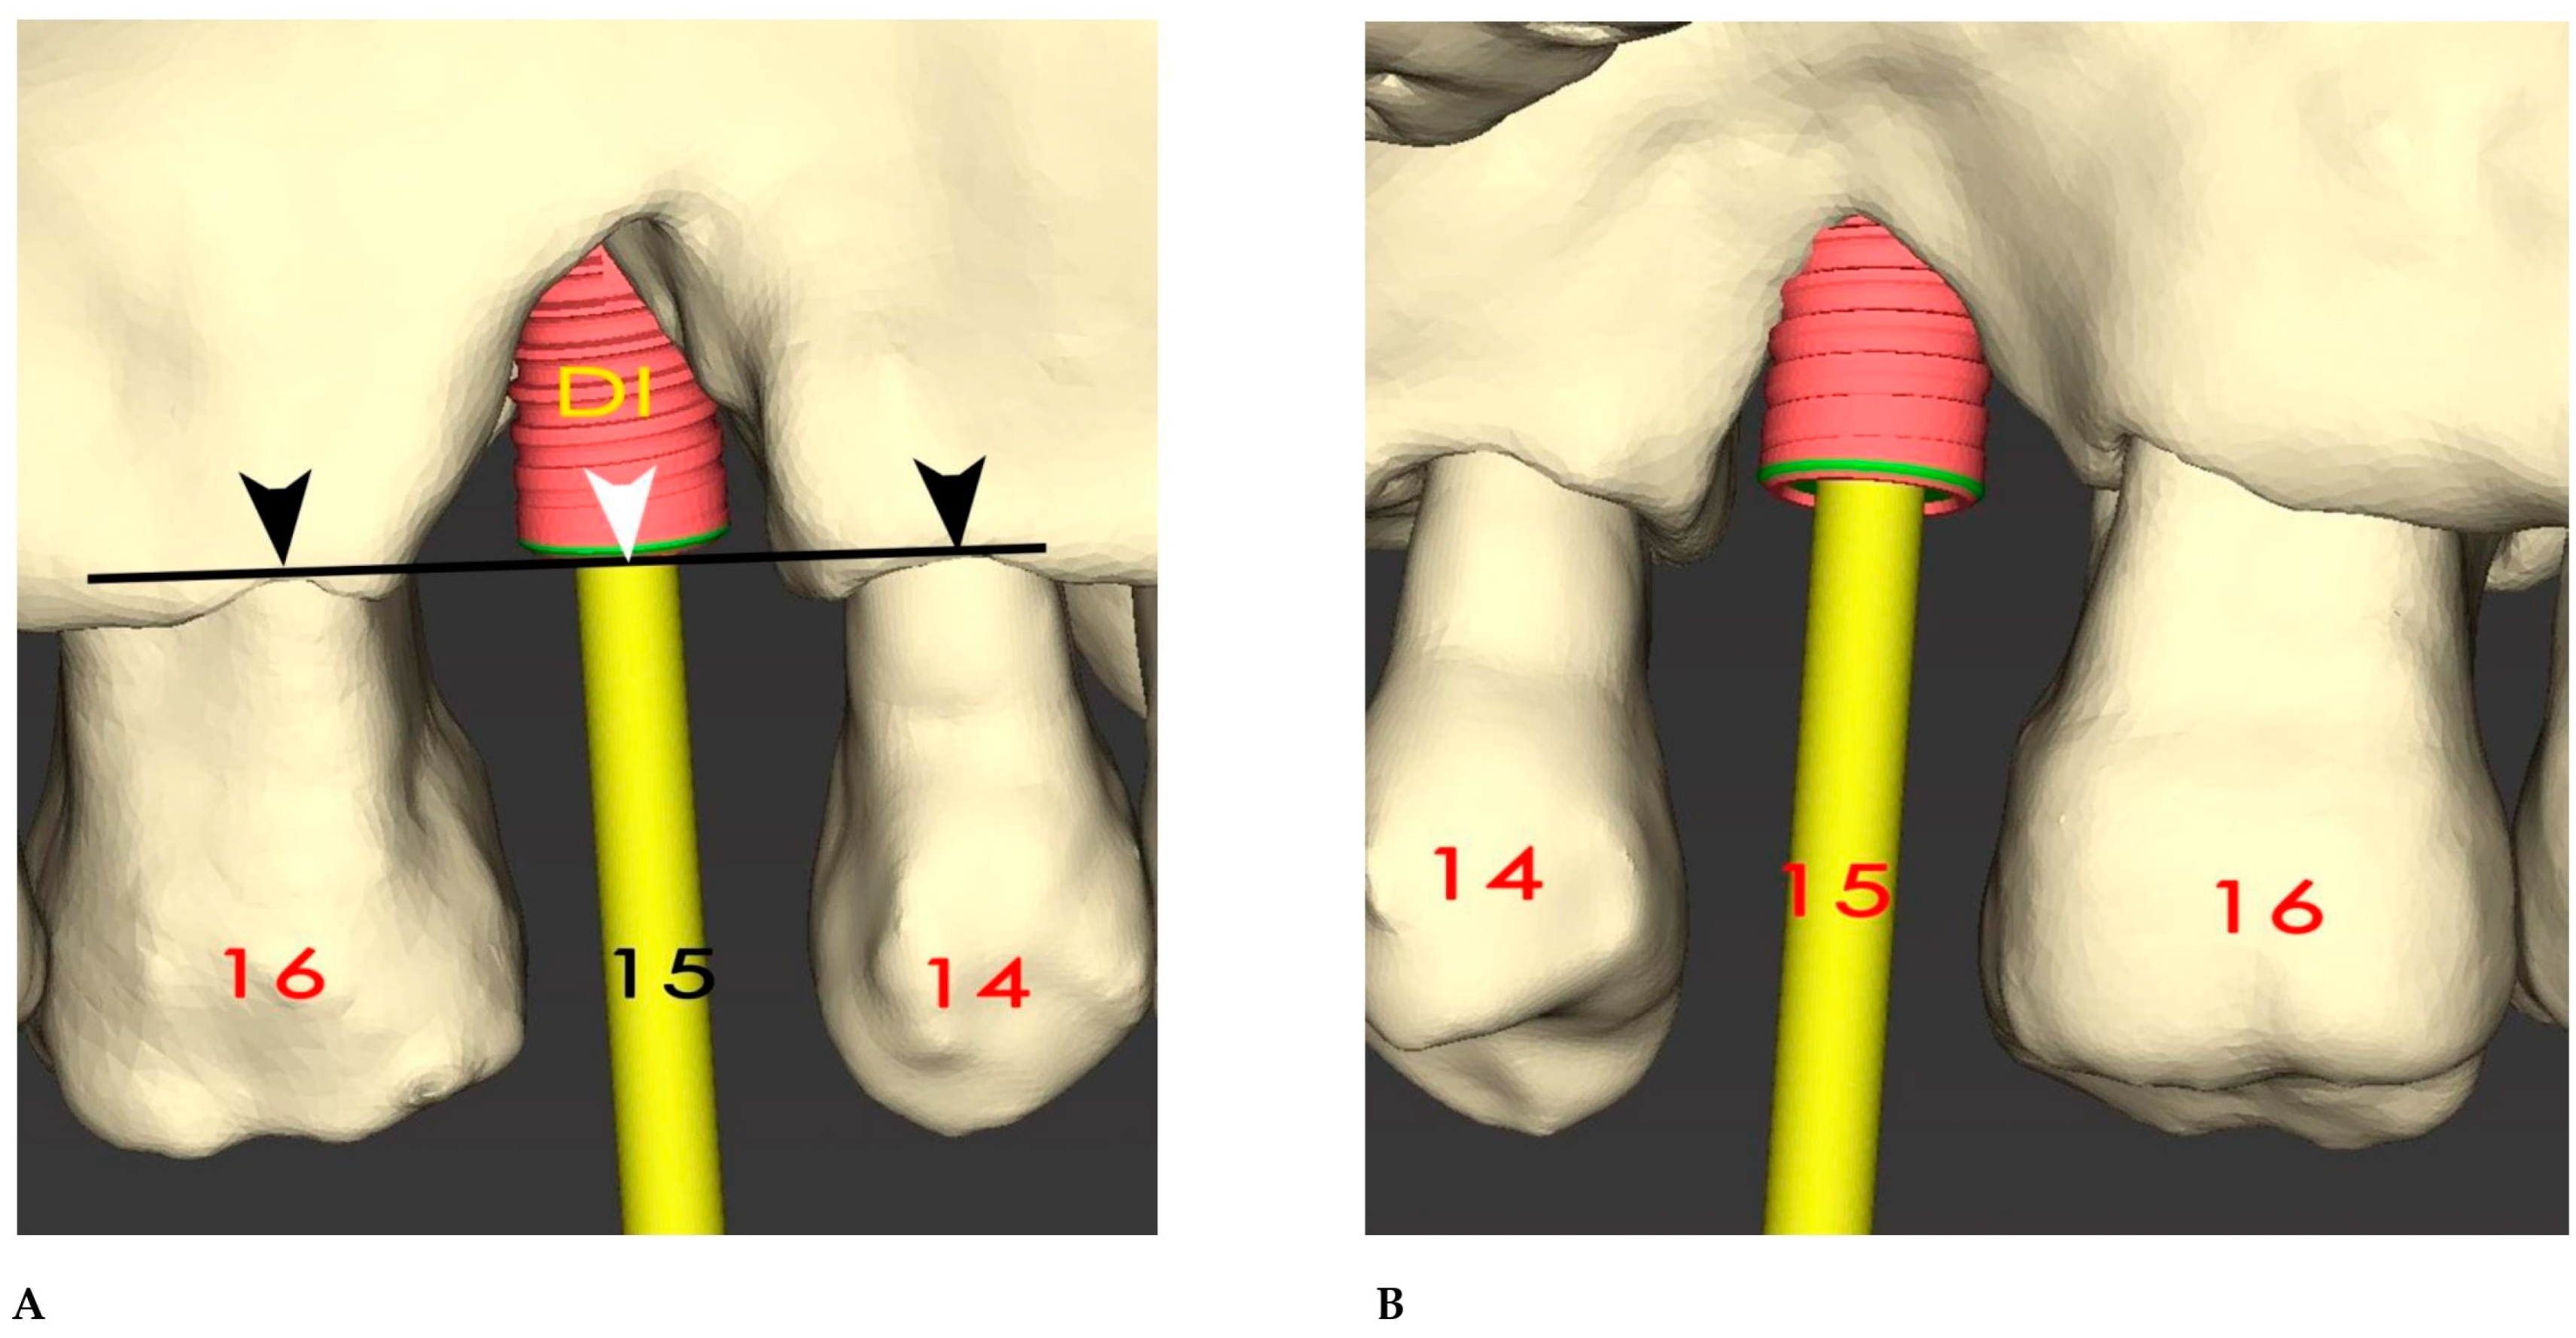

2.1. Surgical Simulation

2.2. GBR Simulation and Mesh Design